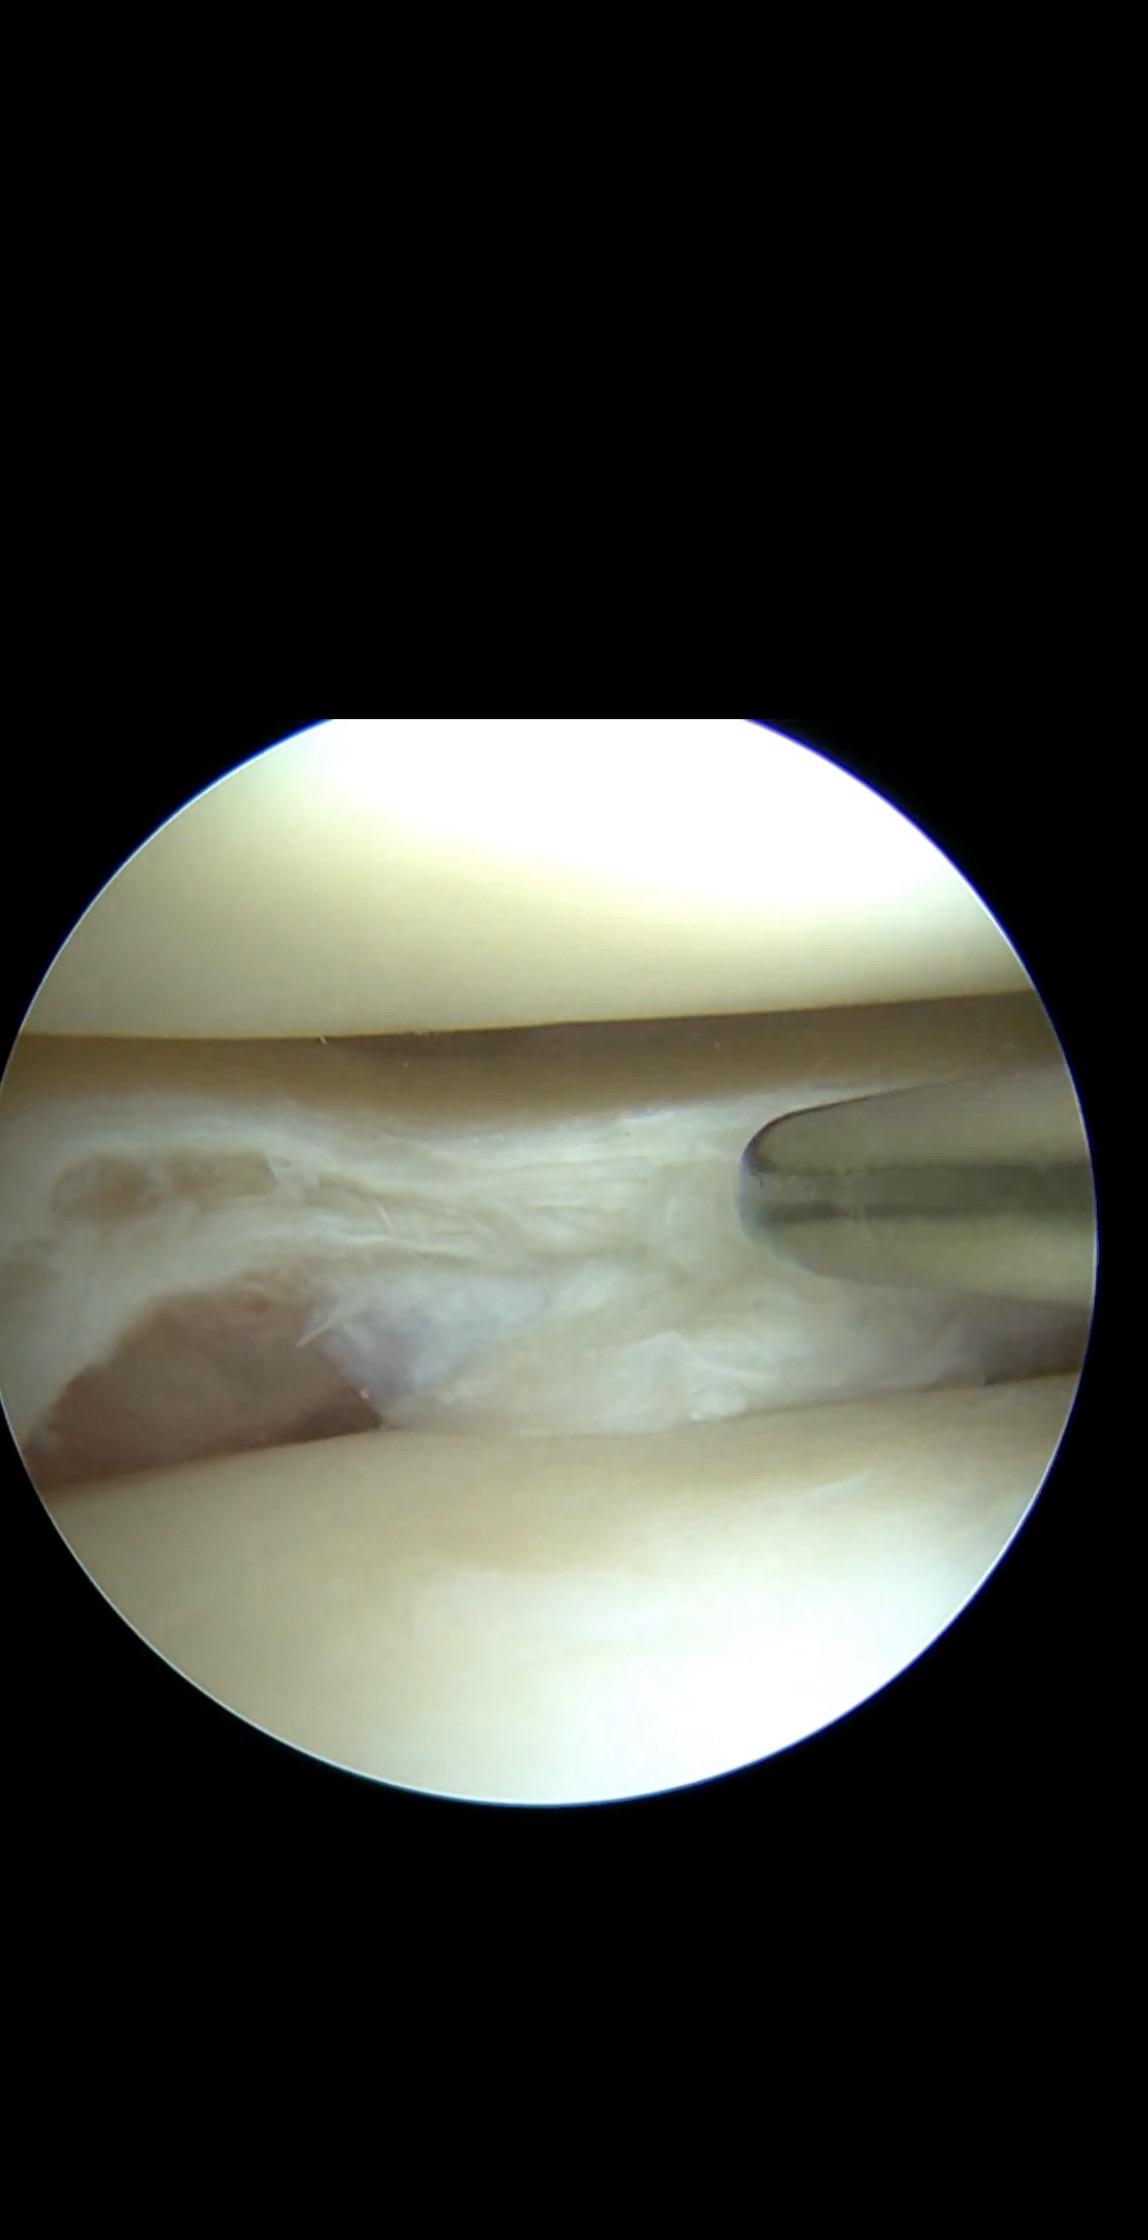

半月板缝合。是一种用于治疗半月板损伤的手术方法。半月板是位于膝关节股骨和胫骨之间的一个半月形软骨样组织,它具有增加稳定性、传递负荷、吸收震荡和润滑关节等作用 。半月板撕裂缝合手术的目的是通过修复损伤的半月板,以恢复其正常功能。